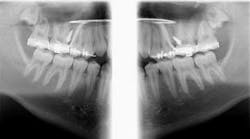

Case report

A healthy 15-year-old male presents to the clinic with an anterior open bite. His case is outlined in the figures below.